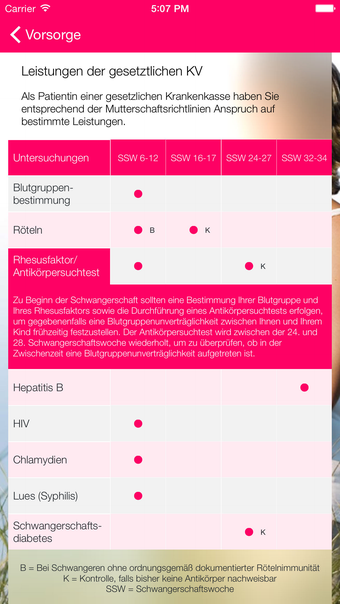

تجعل واجهة التطبيق البديهية والصور الأسبوعية المذهلة للجنين المتطور تجربة الحمل أكثر إشراكًا ومتعة. كما يقدم تقويمًا شاملاً للمواعيد القبلية ونصائح مفيدة لتجنب المخاطر الصحية.

يتضمن iMamaiPapa ثلاثة مجموعات من 40 مقالة لكل من الأمهات والآباء، تغطي مواضيع مثل الصحة ورعاية الطفل والنصائح. كما يتضمن ميزة iBabybauch التي تتيح للمستخدمين التقاط صور يومية / أسبوعية لبطن الجنين وإنشاء فيلم قصير. يمكن للمستخدمين أيضًا الاحتفاظ بيوميات شخصية مع الصور وتخزين البيانات، ومزامنة بيانات الوزن الخاصة بهم اختياريًا بين Apple Health ويوميات iMamaiPapa.